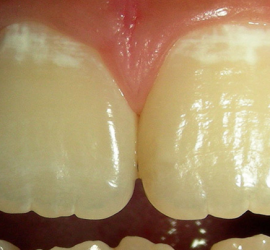

Лечение пульпита. При лечении пульпита перед врачом встают следующие задачи: избавление больного от болевых ощущений, ликвидация инфекционно-токсического очага в пульпе зуба, восстановление формы и функции зуба. Первую помощь больному острым пульпитом может оказать средний медработник или врач любого другого профиля. Она заключается в назначении внутрь обезболивающих препаратов типа анальгина, амидопирина, […]